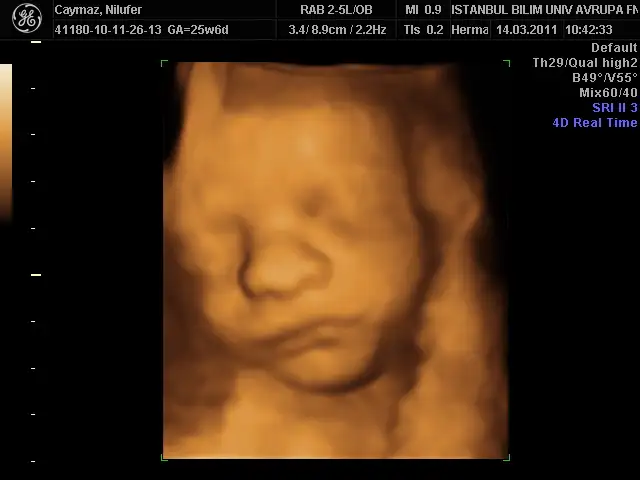

benimki 35 cm 1056 gr olmuş annesinin gülü dr önce rahmi çok ince budu 2,7 mm sonra sıkıştık tuvalalete öyle baktı çok şükür bir problem yokmuş bu sefer yüzünü bizden gizlemedi oğluşumm bence bana benziyor babasını kıl ediyorum bana benziyor diye kız olsa anlarım bana benzesin triplerini de diyor bu erkek banabenzicek diyo bi kıskanıyor bi kıskanıyor çok hoşuma gidiyorr

alın sıze teyzelerı suratsız oglum:))